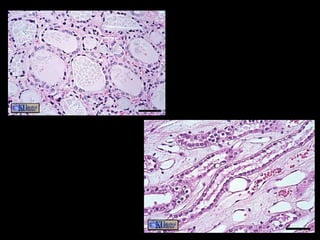

Simple Cuboidal Epithelium Structure Single layer of cube shaped cells Function Secretion and transportation in glands, filtration in kidneys Location Glands and ducts (pancreas & salivary), kidney tubules, covers ovaries

Simple Cuboidal EpitheliumStructure Single layer of cube shaped cells Function Secretion and transportation in glands, filtration in kidneys Location Glands and ducts (pancreas & salivary), kidney tubules, covers ovaries